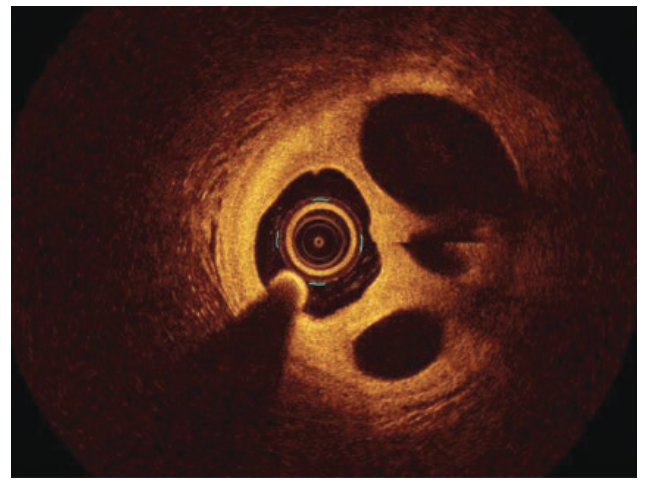

Coronary angiography demonstrated an unobstructed left main, and normal left anterior descending (LAD) artery and left circumflex (Figure 2). The right coronary artery (RCA) had an intraluminal defect extending from the ostium to the distal vessel (Figure 3, Video 1). Optical coherence tomography (OCT) was performed to further delineate this finding, and showed multiple channels with preserved intima and no evidence of plaque rupture (Figure 4, Video 2). Based on OCT, the diagnosis of woven coronary artery (WCA) was established. The decision was made to proceed with percutaneous coronary intervention (PCI) of the RCA with 3 overlapping drug-eluting stents from distal to proximal vessel (Figure 5). Post-PCI OCT was done and showed appropriate stent expansion. The patient was discharged on dual antiplatelet therapy (DAPT) in a stable clinical condition.

In our case, the mottled, hazy appearance of the RCA raised the possibility of dissection versus recanalized thrombus, based on angiography. Wiring can be particularly challenging given the multiple channels. As such, a hydrophilic guidewire with polymer coating (Hi-Torque Pilot 50, Abbott Vascular) was used, along with meticulous handling of the torque device, in order to negotiate the lesion safely. OCT was crucial to refute other diagnostic possibilities and establish the definitive diagnosis of WCA. Although WCA is usually considered a benign entity, acute coronary syndrome and even sudden cardiac death have been reported as possible sequelae.3 In our patient, the lesion extended from the ostial RCA to the distal vessel and before the bifurcation. Given the patient’s ongoing chest pain and rising cardiac biomarkers, PCI was warranted.